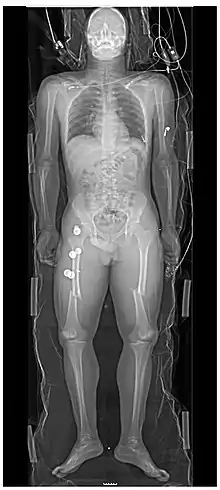

Projectional radiography, also known as conventional radiography,[1] is a form of radiography and medical imaging that produces two-dimensional images by x-ray radiation. The image acquisition is generally performed by radiographers, and the images are often examined by radiologists. Both the procedure and any resultant images are often simply called "X-ray". Plain radiography or roentgenography generally refers to projectional radiography (without the use of more advanced techniques such as computed tomography that can generate 3D-images). Plain radiography can also refer to radiography without a radiocontrast agent or radiography that generates single static images, as contrasted to fluoroscopy, which are technically also projectional.

- Hard tissues such as bone require a relatively high energy photon source, and typically a tungsten anode is used with a high voltage (50-150 kVp) on a 3-phase or high-frequency machine to generate bremsstrahlung or braking radiation. Bony tissue and metals are denser than the surrounding tissue, and thus by absorbing more of the X-ray photons they prevent the film from getting exposed as much.[11] Wherever dense tissue absorbs or stops the X-rays, the resulting X-ray film is unexposed, and appears translucent blue, whereas the black parts of the film represent lower-density tissues such as fat, skin, and internal organs, which could not stop the X-rays. This is usually used to see bony fractures, foreign objects (such as ingested coins), and used for finding bony pathology such as osteoarthritis, infection (osteomyelitis), cancer (osteosarcoma), as well as growth studies (leg length, achondroplasia, scoliosis, etc.).

- Soft tissues are seen with the same machine as for hard tissues, but a "softer" or less-penetrating X-ray beam is used. Tissues commonly imaged include the lungs and heart shadow in a chest X-ray, the air pattern of the bowel in abdominal X-rays, the soft tissues of the neck, the orbits by a skull X-ray before an MRI to check for radiopaque foreign bodies (especially metal), and of course the soft tissue shadows in X-rays of bony injuries are looked at by the radiologist for signs of hidden trauma (for example, the famous "fat pad" sign on a fractured elbow).